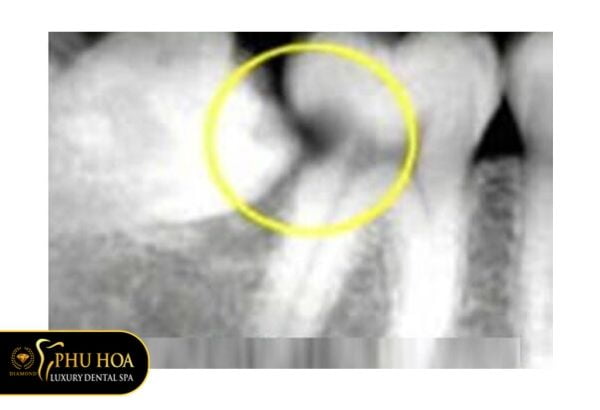

Răng khôn gây biến chứng sâu răng kế bên

Tiếp tục là một hình ảnh răng khôn gây sâu sang răng bên cạnh. Tuy nhiên, khi nhìn vào hình bạn thấy rằng răng bên cạnh đã bị sâu đến tủy. Trong khi đó, chiếc răng kế bên là răng số 7, là răng hàm rất quan trọng giúp việc ăn nhai được ổn định.

Vì thế nếu chiếc răng khôn không được nhổ sớm có thể gây hư hại răng số 7, khiến chiếc răng này khó có thể giữ lại được.